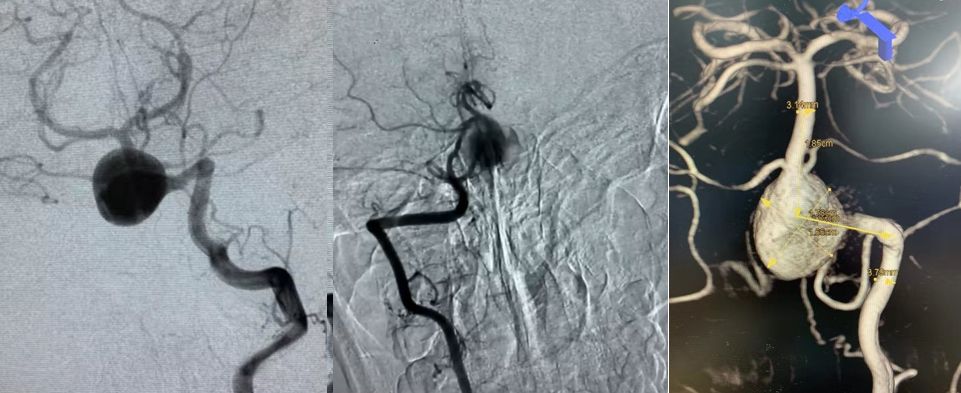

2019.5.25外院DSA

通过造影可以看到,动脉瘤主体位于右侧椎动脉,左侧椎动脉也有累及,不过左侧椎动脉PICA以远的部分纤细,考虑可以牺牲掉而不会影响基底动脉血供,但可以部分减少动脉瘤压力。左侧椎动脉为优势椎动脉,则应用PED装置保护并重建之。

经左椎动脉造影可见椎-基底动脉汇合部巨大动脉瘤,双侧椎动脉均有累及,以左侧椎动脉为主,右侧PICA与动脉瘤有一定距离,基底动脉稍受累及,AICA距离动脉瘤较近。